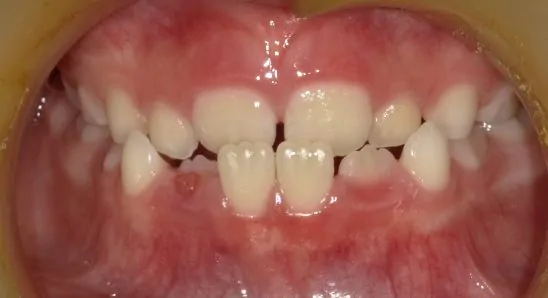

治療後

口腔衛生指導後、マウスピース型矯正歯科装置にて歯の移動を行いました。右上の犬歯の生えるスペースがありませんでしたから、歯を移動することで排列スペースをつくっています。Ⅰ期治療が終了したところで、ご本人と保護者の方が満足されているため経過観察中です。すべての永久歯が萌出したところで、セカンドフェーズ(Ⅱ期治療)を行うか判断する予定です。

永久歯の抜歯なし